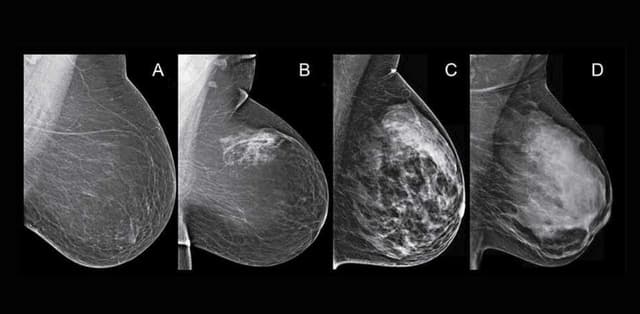

U nang tuyến vú phát hiện như thế nào?

U nang tuyến vú rất hiếm liên quan đến nguyên nhân ung thư, tuy nhiên bệnh có thể ảnh hưởng đến sức khỏe, tinh thần và ngoại hình của phụ nữ. Vậy u nang tuyến vú phát hiện như thế nào? Hãy cùng Thu Cúc TCI tìm hiểu thông qua bài viết sau đây. 1. […]